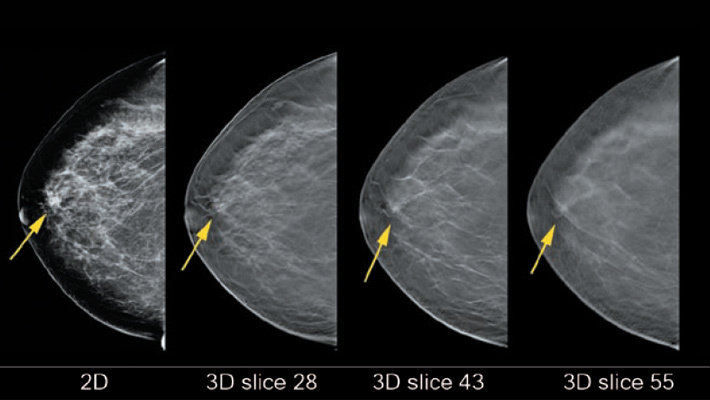

Mammograms for breast pain in 78% of patients.

94% of which were diagnostic mammograms

A mammographic finding in the area of breast pain was seen in four of 625 mammograms.